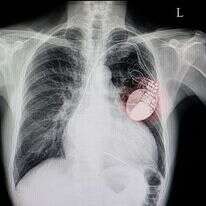

למה השתילו לנתניהו קוצב לב? קרדיולוג בכיר מסביר"חשבו שזה התייבשות אבל זה לא מה שהיה", לאחר ההליך הרפואי שעבר נתניהו, פנינו אל פרופ' דוד לוריא, מהמרכז הרפואי הדסה עין כרם שיסביר לנו על הגורמים והסיכונים בהשתלת קוצב לבישי אלמקייס־אלרםישי אלמקייס־אלרם

רופאי נתניהו: "זו הסיבה שהזמנו את ראש הממשלה בדחיפות"ראש הממשלה עבר הליך השתלת קוצב לב. פרופ' רועי בינרט: "זיהו במנטר התת עורי שהשתלנו בגופו שבוע קודם לכן, הפרעת קצב זמנית שארעה במהלך מוצאי שבת"ישי אלמקייס־אלרםישי אלמקייס־אלרם